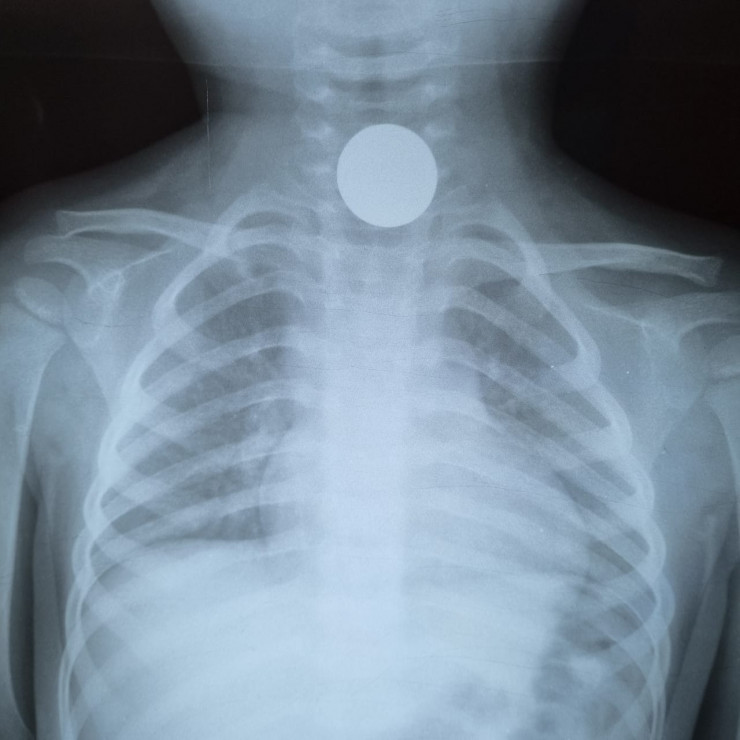

"В основном дети заглатывают инородные предметы при игре или приеме пищи. Например, монеты, плоские батарейки, бусинки, булавки, косточки от курицы и многое другое. Самое страшное в такой ситуации - затрудненность дыхания или непроходимость пищевода", - рассказывает он.

Врач рассказал, что в таких случаях проводится эндоскопия. Процедура не очень приятная, поэтому в основном делают ее под наркозом.

"Например, из кишечника 4-летнего малыша вытащили кольцо от связки ключей. Родители три недели не догадывались, что их ребенок проглотил его. Хотя он жаловался на боли в животе, рвоту. Потом обратились к нам. Под общим наркозом на ФГДС мы обнаружили инородное тело в 12-перстной кишке и извлекли его. Был еще случай недавно: мы вытащили из дыхательных путей 14-летнего подростка фонарик от зажигалки. Примечательно то, что юноша месяц ходил и никому не рассказывал об этом, пока при обследовании на рентгене случайно не обнаружили инородное тело в дыхательных путях", - рассказал Серик Нусипкожаев.

Врач предупреждает, что симптомы попадания инородного тела в дыхательные пути схожи с симптомами простуды: кашель, рвота, хрипы, а при попадании предмета в ЖКТ - рвота, боль в животе.